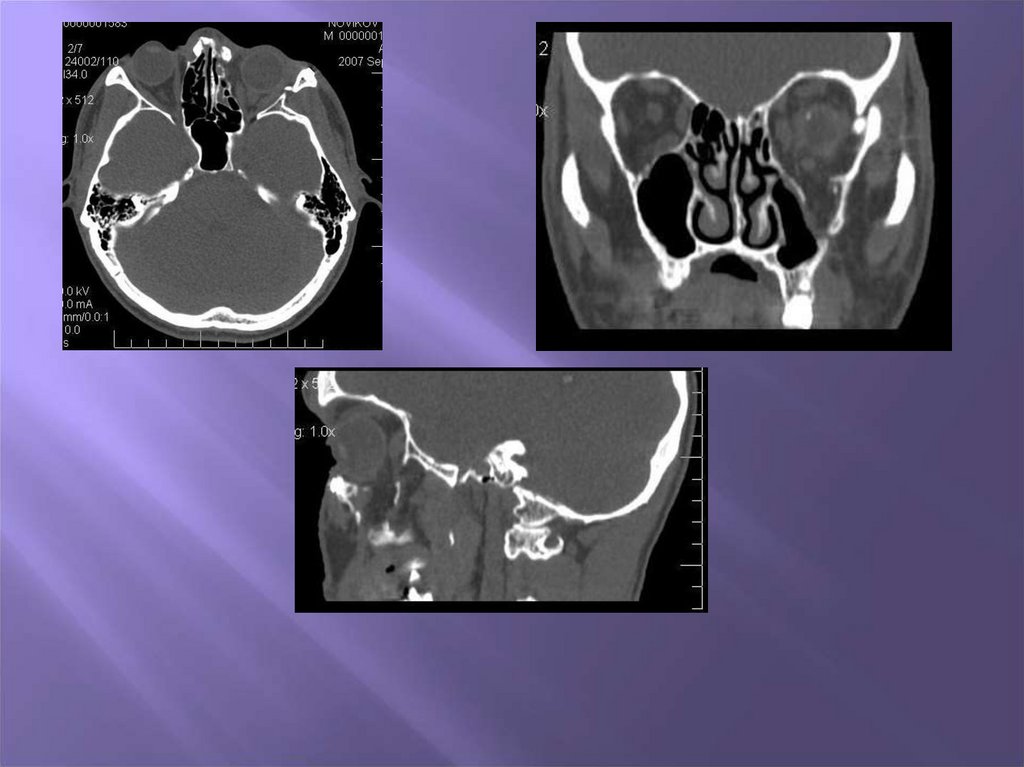

4. Методы обследования пациентов с врожденными и приобретенными дефектами и деформациями скуловой кости , дуги и носа

1. Клинический

2. Рентгенологический

3. Компьютерная томография

4. Изготовление стереолитографической

модели

38. Изготовление стереолитографической модели